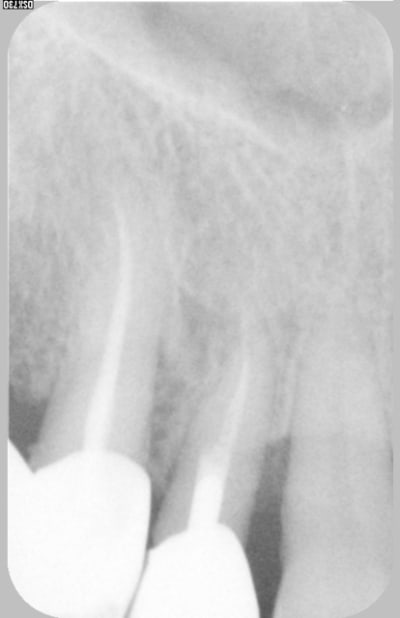

Excusez moi de revenir dans ce débat à fleurets non mouchetés, mais guttaman, qu'est ce en fait. Il y avait une patiente au début de ce post, non ?

Et la soluce est.......poche en linguale...la preuve sur la RX. Comme quoi, même en cherchant une fois, ça suffit pas toujours. Dans le cas présent, la sonde m'a induit en erreur...mais pas le cône de gutta !! (encore une raison d'adorer ce matériau ! ;-) )

Pour le traitement : pour l'instant, abstention thérapeutique car il y a d'autres soucis (cf 2° radio jointe, qui n'est qu'un exemple). Et en plus je sais pas trop quoi lui proposer pour une poche comme ça.

La patiente à une hygiène très correcte, d'autres problèmes paro localisés et c'est une dent support de crochet...

Donc soit purement parodontal sans que la dent y soit pour quelque chose, soit fêlure longitudino-transversale qui crée une sorte de fistule desmodontale en regard.

Même si la dent n'est pas sensible aux variations thermiques, je penche pour cette deuxième possibilité (d'où abstention thérapeutique pour l'instant).

pour ta patiente, effet de pompe du bras de crochet sur la muqueuse linguale et poche serpengineuse en plus du problème de la charge puisque la dent supporte un crochet pour une selle distale...